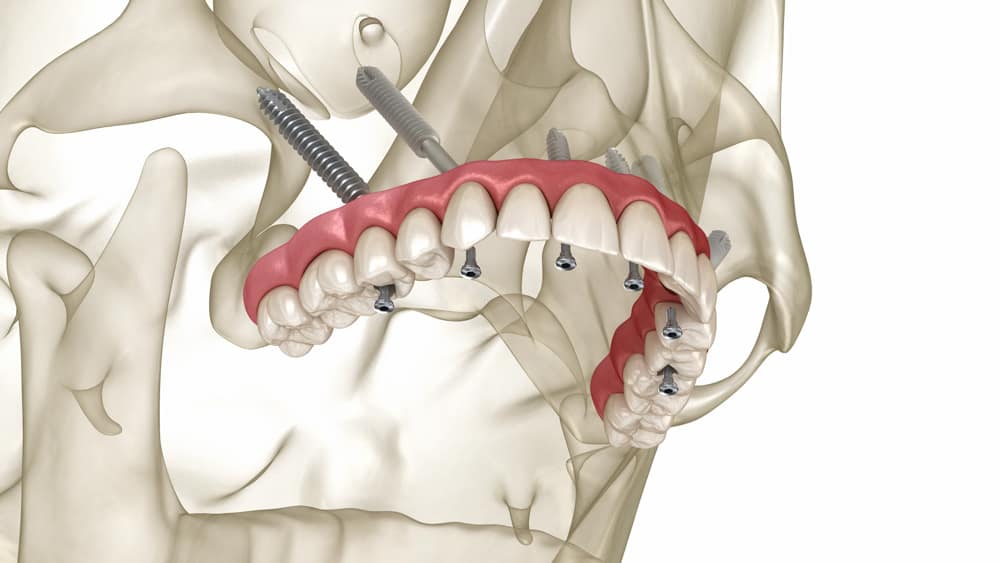

Los implantes cigomáticos son implantes de titanio que son significativamente más largos que los implantes convencionales (pueden medir entre 30 mm y 52.5 mm).

A diferencia de los implantes tradicionales, que se anclan en el hueso alveolar maxilar (el hueso donde estaban los dientes), los implantes cigomáticos se extienden y se fijan en el Hueso Cigomático (o Pómulo).

Los implantes cigomáticos son implantes de titanio que son significativamente más largos que los implantes convencionales (pueden medir entre 30 mm y 52.5 mm).

3.- Deseo de Carga Inmediata: La estabilidad inherente en el hueso cigomático de alta densidad permite a menudo la colocación de una prótesis fija provisional el mismo día de la cirugía (Carga Inmediata).

La principal ventaja de este protocolo, además de la función masticatoria, es la reducción drástica en el tiempo total del tratamiento.

El tratamiento puede completarse y ser funcional en días o semanas (gracias a la carga inmediata).